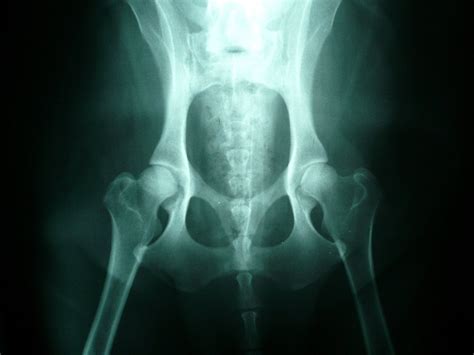

Na snímku dysplatické kyčle vás upoutá hlavně hlavice stehenní kosti, která není pevně a dostatečně hluboko usazena v kloubní jamce; nebo skutečnost, že hlavice a jamka nejsou na povrchu hladké, ale zdeformované. To může způsobit opotřebení kloubu a velké bolestivé tření při pohybu. Kyčel pak trpí nadměrnou zátěží a je náchylný na vytvoření zánětu, díky kterému se navíc může vyvinout osteoartróza, která je na RTG snímku rozpoznatelná jako malé úlomky kostí, ničící pak dále kloub.

Pro správnou interpretaci onemocnění kyčelních a loketních kloubů je nutné RTG vyšetření, které musí splňovat konkrétní náležitosti. Zvíře musí být minimálně sedované, lépe v celkové narkóze, aby bylo možné zvíře správně polohovat. Při rentgenování kyčelních kloubů pacienta umístíme do hřbetní polohy, zafixuje se hrudník a zadní končetiny se musí držet navzájem rovnoběžně. K fixaci používáme speciální kolébku. Na základě takto správně projekčně a expozičně zhotoveného snímku se posuzuje jednotlivá kritéria kyčelních kloubů.